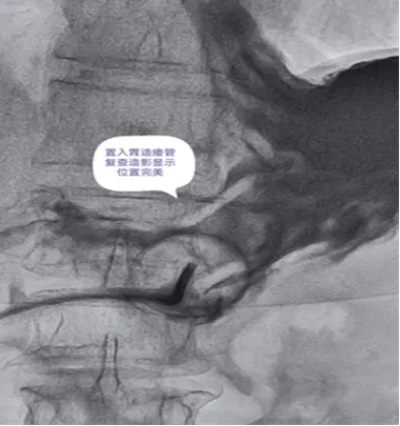

DSA引导下经皮胃造瘘术,是在数字减影血管造影(DSA)这个“透视眼”的实时可视化导航下,于患者腹壁上建立一个仅 3-5毫米 的微小穿刺点。通过这个“针眼”,医生精准地将一根营养管直接置入胃部,建立起一条直达的营养通道。

整个过程就像一次精准的“导航穿刺”,全程操作便捷、创伤小,却能完美替代传统的鼻饲管,为患者提供长期、稳定、安全的营养支持。

医院临床实践中就有典型案例:一名65岁食道癌伴淋巴结转移患者,因食道狭窄无法插入胃镜,且体质虚弱难以耐受全麻手术,团队借助DSA精准导航,仅用10分钟便完成手术,局部麻醉下患者全程无明显不适,术后1天即可通过造瘘管补充营养,为后续抗肿瘤治疗顺利开展奠定了坚实基础。